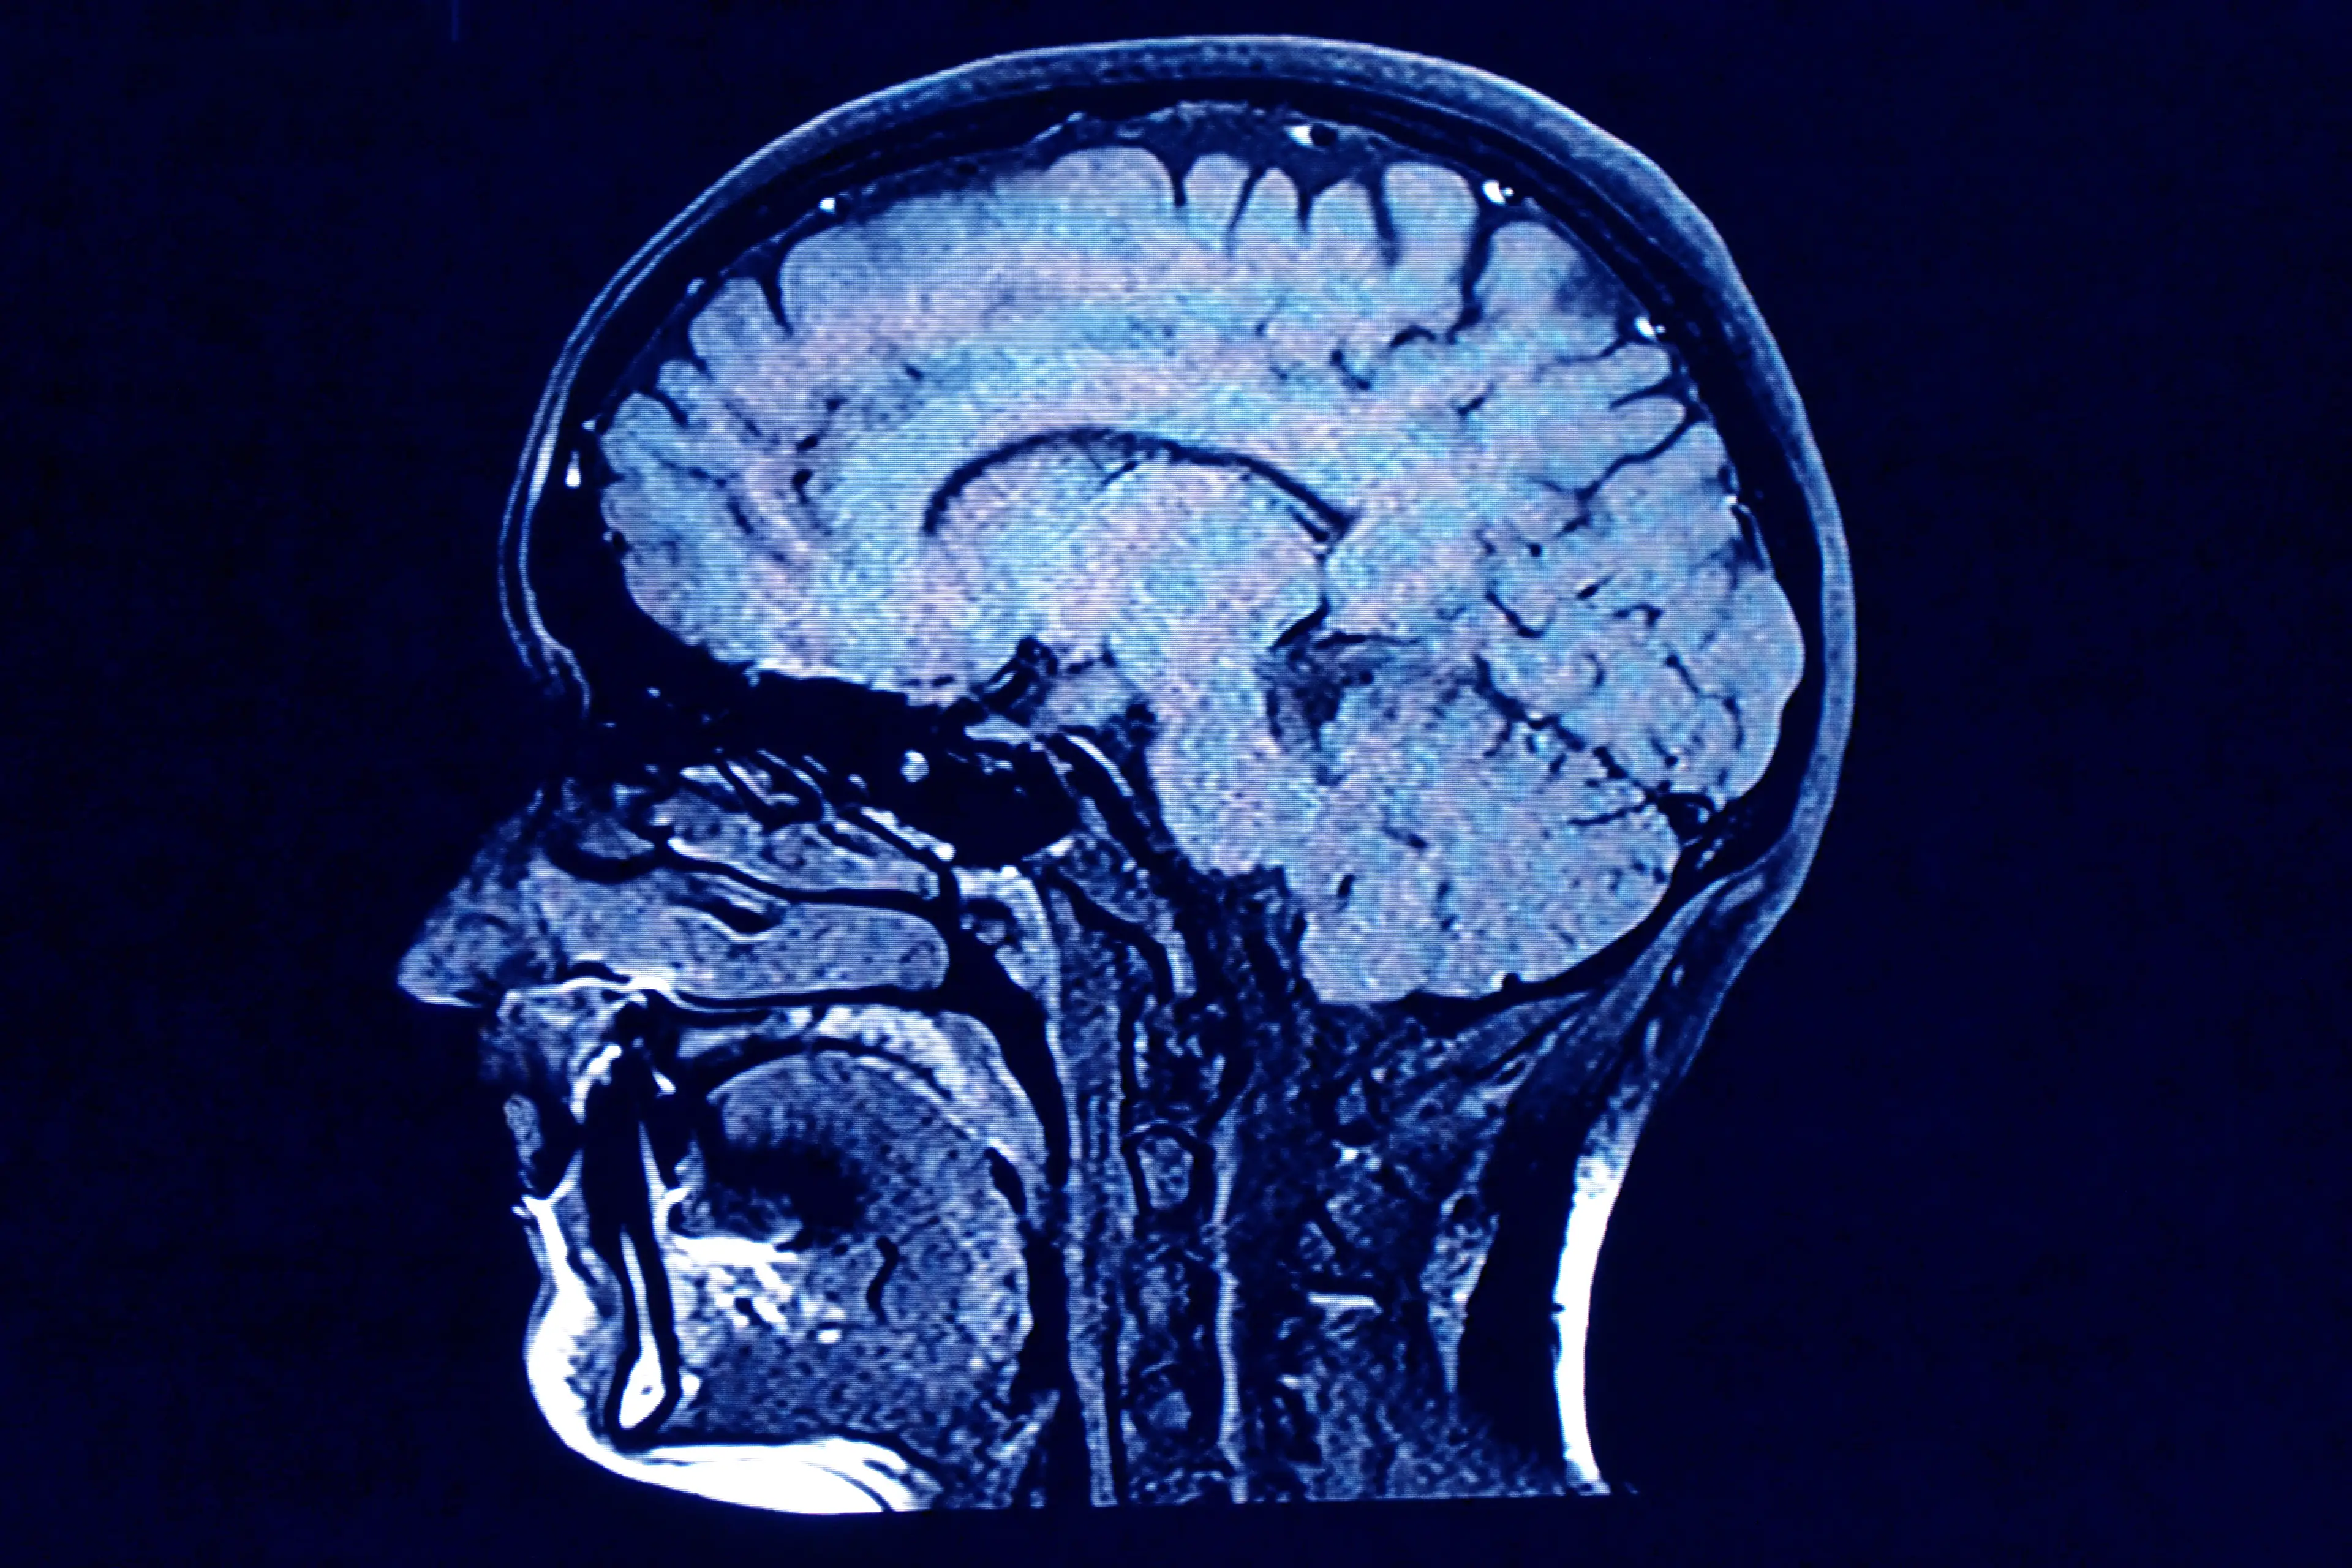

In layperson's terms, Neuralink is researching how to insert chips into people's brains as a way to help restore lost limb function.

Essentially, these volunteers will have a hole drilled in their skull and a device inserted by a robot.

It will be made up of the chip, about the size of a quarter, and tiny wires and electrodes thinner than a human hair.